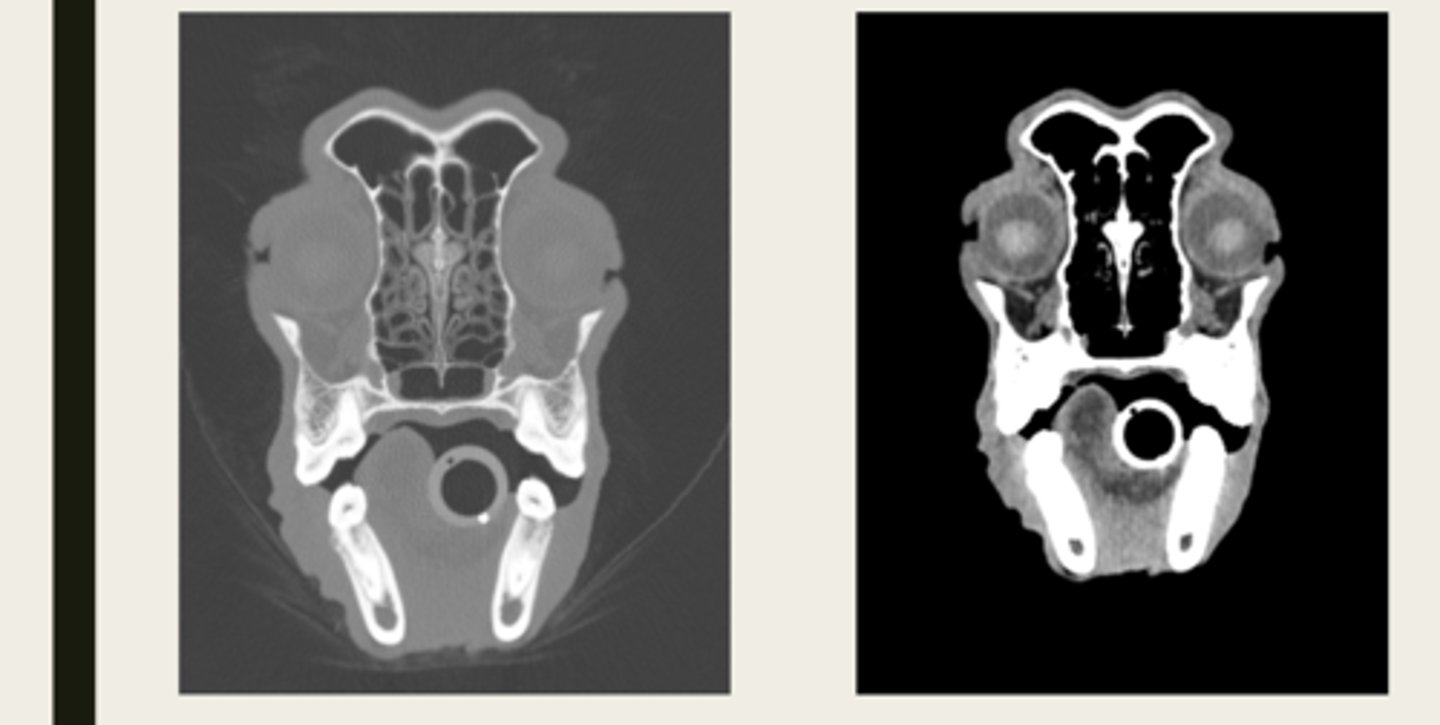

left- soft tissue window

right- bone window

ID the CT windows

left- pre contrast

right- post contrast

window- soft tissue window

which CT images are pre and post contrast? what type of window is being shown in both?

left- T1 weighted

right- T2 weighted

which image is T1 weighted and which is T2 weighted?

left- T1 weighted

right- T2 weighted

which MRI image is T1 or T2 weighted?

left- pre contrast

right- post contrast

which MRI is pre and post contrast?